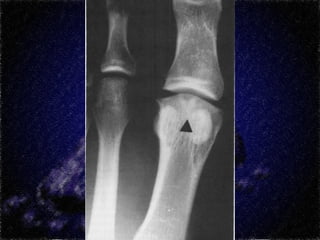

Cirurgia de Bonney e Kessel (Moberg)

Osteotomia com cunha para dorsiflexão

Base da falange proximal

Adolescentes e pctes no estágio inicial da dça

Não deve haver lesões degenerativas

Tratamento

Cirúrgico